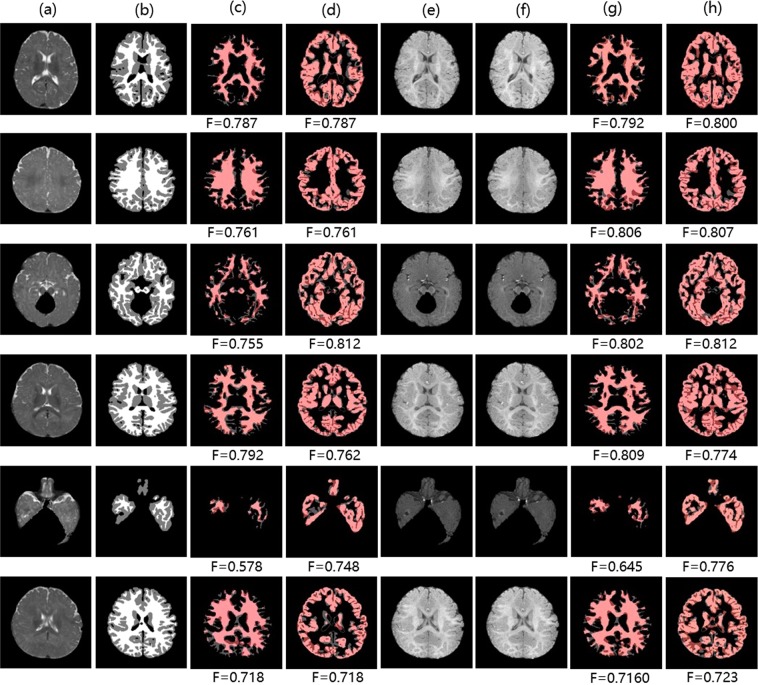

As shown in Tables 6, cross-modality information from -Flair and images contributes improvements to tumor segmentation of T1 images (7.89% and 6.32% of tumors respectively). Likewise, Table 7 shows that cross-modality information from images leads to improvements of wm and gm segmentation of T2 images (3.08% of wm and 2.09% of gm). We also add cross-modality information from real modalities to make an upper bound. We observe a minor gap between results of TMS and the upper bound though our translated modalities are very close to real modalities. It is explicable by the presence of abnormal tissue anatomy (eg. tumors) and the cortex in MR images. The tumors are diffuse and even a small difference in the overlap can cause a low value for the Dice. In addition, in some finer cortex regions (unlike large homogeneous gray matter and white matter), our approach may produce some relatively coarse images, leading to a lower Dice. Moreover, our approach aims to help incorporate extra cross-modality information for more accurate segmentation rather than replace the real images. Overall, TMS outperforms the traditional FCN method when favorable cross-modality information is adopted. Figures 9 and 10 visualize some samples of our segmentation results on BraTs2015 and Iseg2017 respectively.

Figure 9.

Samples of tumor segmentation results on BraTs2015: (a,d,e,g,h) denote T1 image, T2 image, image, T2-Flair image, -Flair image. (b) Denotes ground truth segmentation label of T1 image. (c,f,i) Denote tumor segmentation results of T1 image using the FCN method, TMS (adding cross-modality information from image), TMS (adding cross-modality information from -Flair image). Pink: true regions. Grey: missing regions. Dark red: false regions.

Figure 10.

Samples of brain structure segmentation results on Iseg2017: (a,e,f) denote T2 image, T1 image, image. (b) Denotes ground truth segmentation label of T2 image. (c,d) Denote white matter and gray matter segmentation results of T2 image using the FCN method respectively. (g,h) Denote white matter and gray matter segmentation results of T2 image using TMS (adding cross-modality information from image) respectively. Pink: true regions. Grey: missing regions. Dark red: false regions.